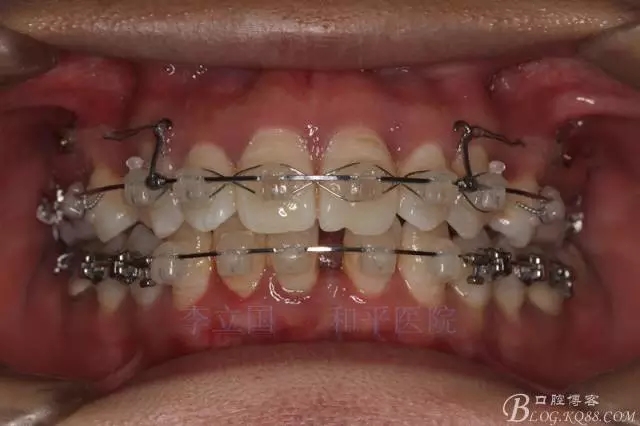

”嘴凸牙不凸”病例治療要點(diǎn)

患者主訴前突。

1.患者上前牙直立,面型前突,典型的嘴凸牙不吐,關(guān)鍵是前牙轉(zhuǎn)矩控制,建議使用高轉(zhuǎn)矩托槽。

2.磨牙關(guān)系一側(cè)完全遠(yuǎn)中,一側(cè)遠(yuǎn)中尖対尖,采用兩個(gè)上4,一個(gè)下1的拔牙模式。

4.使用長(zhǎng)牽引鉤,使?fàn)恳咏项M骨阻抗中心,防止上頜骨的順時(shí)針旋轉(zhuǎn)。

5.回收過程中,上下前牙輕搖椅,防止覆合加深。